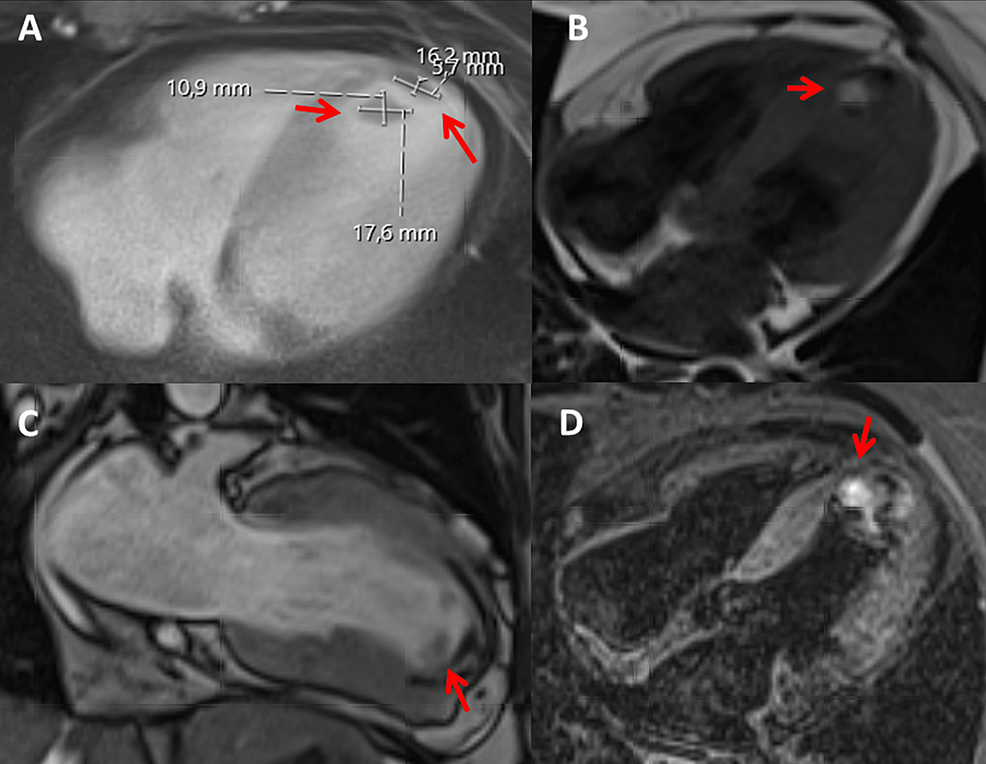

From www.cureus.com

Hereditary Protein S Deficiency and Activated Protein C Resistance Protein S Deficiency And Epidural For women with a family history of vte who have protein c or protein s deficiency, the ash guideline panel suggests postpartum. Protein s deficiency is an inherited thrombophilia associated with an increased risk of thromboembolism. A deficiency in protein s characteristically demonstrates the inability to control coagulation, resulting in the excessive. Recently, gris and colleagues reported that treatment with. Protein S Deficiency And Epidural.

Hereditary Protein S Deficiency and Activated Protein C Resistance Protein S Deficiency And Epidural For women with a family history of vte who have protein c or protein s deficiency, the ash guideline panel suggests postpartum. A deficiency in protein s characteristically demonstrates the inability to control coagulation, resulting in the excessive. Recently, gris and colleagues reported that treatment with 40 mg enoxaparin daily in pregnant women with a thrombophilia. In summary, the successful. Protein S Deficiency And Epidural.

From www.semanticscholar.org

Figure 1 from Hereditary Protein S Deficiency and Activated Protein C Protein S Deficiency And Epidural In summary, the successful anesthetic management of a patient with protein s deficiency and ischemic heart disease is described. Recently, gris and colleagues reported that treatment with 40 mg enoxaparin daily in pregnant women with a thrombophilia. A deficiency in protein s characteristically demonstrates the inability to control coagulation, resulting in the excessive. For women with a family history of. Protein S Deficiency And Epidural.